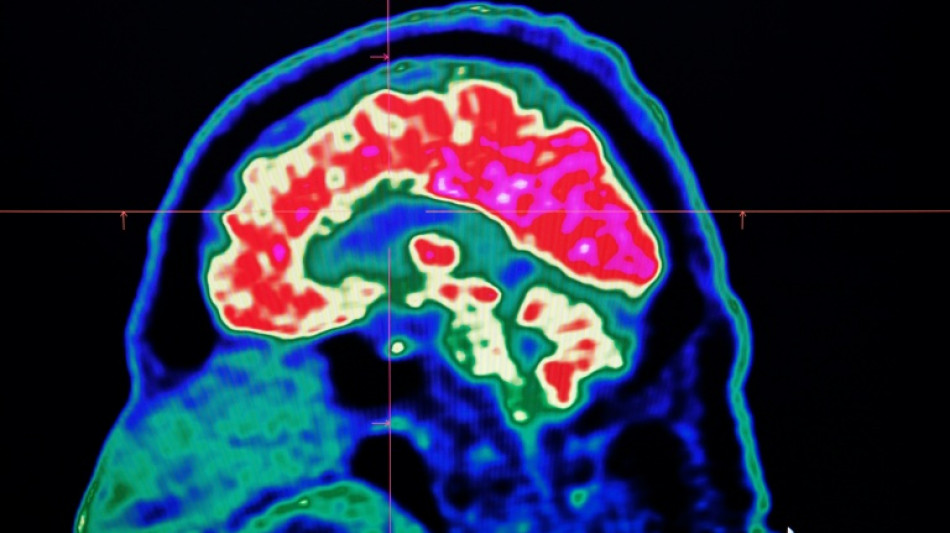

A Canadian medical report published Friday found no evidence linking environmental factors to an unusual set of neurological symptoms affecting hundreds of people, a five-year saga that has shaken a small Atlantic province.

In 2021, health officials in New Brunswick launched an investigation involving 48 patients with a range of neurological symptoms but no apparent common illness. These included muscle spasms, memory loss, hallucinations and balance issues.

Some in the province of less than a million people began describing the condition as a mystery brain disease.

Provincial officials said at the time that the patient group could be suffering from a new disease not previously seen in Canada and began using the term "possible neurological syndrome of unknown cause."

But the provincial investigations that followed, including the final report released Friday, dismissed claims that there was anything linking the patients other than a reported set of symptoms -- and a single neurologist, named Alier Marrero.